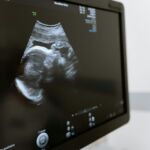

Pregnancy is a miraculous journey marked by various stages of fetal development. Ultrasound scans play a pivotal role in monitoring and ensuring the well-being of both the mother and the developing baby. In this guide, we will explore the stages of pregnancy and the frequency of ultrasound examinations, shedding light on the significance of each stage in understanding and tracking fetal growth.

In the UK, the National Health Service (NHS) plays a crucial role in monitoring and ensuring the well-being of both the mother and the developing baby through a standardized ultrasound schedule. NHS’s recommended scans, which include early pregnancy scans at 10 and 14 weeks and a mid-pregnancy scan at 18 to 21 weeks.

Ultrasound Frequency: During the first trimester, ultrasounds are typically performed around 6-9 weeks. An early ultrasound confirms the pregnancy, establishes the gestational age, and verifies the presence of a heartbeat. The NHS typically advice an early pregnancy scan between 10-14 weeks.

Ultrasound Frequency: The second trimester commonly involves the anatomy scan around 18-22 weeks, which assesses the baby’s growth, checks for structural abnormalities, and provides an opportunity for parents to learn the baby’s gender. The NHS also recommends a scan between 18 and 21 weeks, called a mid-pregnancy scan.

Ultrasound Frequency: In the later weeks of pregnancy, additional ultrasounds may be recommended based on individual circumstances. This can include growth scans to monitor the baby’s size and amniotic fluid levels.